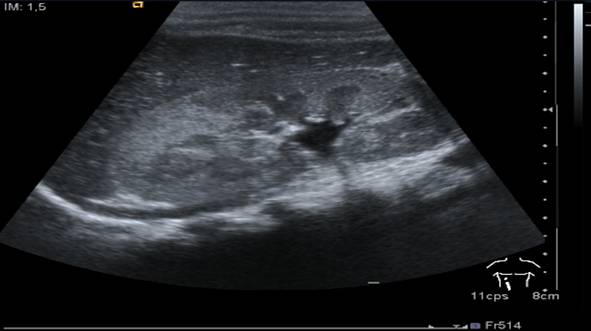

Figura X-7

Figure X-7